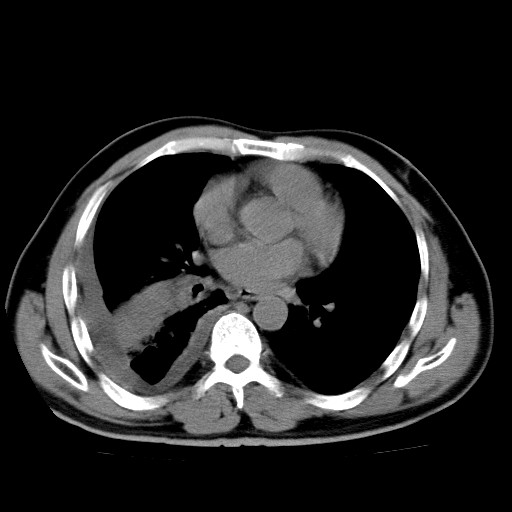

男,54岁,咳嗽,右侧胸痛10天。肺窗>150k,传不了

右肺中心型肺癌并右下肺不张,右侧胸膜纵隔转移。

右中央型肺癌并右肺下叶不张,纵隔内及右胸膜转移,右胸腔积液

考虑   右肺癌伴右下肺部分不张,阻塞性肺炎,纵隔淋巴结增大,右侧胸腔积液其他待排

考虑右肺下叶中央型肺癌并右肺下叶不张,纵隔淋巴结内及右胸膜转移。建议增强。

右下叶大片实变,肺门未见明显肿块影。有胸腔积液和纵隔内肿大淋巴结影。没有增强和肺窗,不好定。

考虑:1、右下叶周围型肺癌伴胸膜、纵隔淋巴转移?